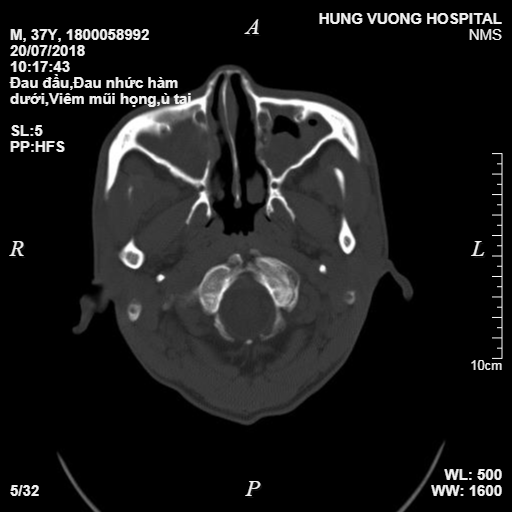

Bệnh nhân được chỉ định chụp CT sọ não và nội soi mũi, xoang, kết quả CT Scanner cho thấy hình ảnh nấm xoang cả hai bên, nội soi 2 bên xoang có nhiều dịch mủ trắng như sữa. Qua các kết quả cận lâm sàng các bác sỹ chẩn đoán bệnh nhân bị nấm xoang hàm, chỉ định phẫu thuật nội soi mũi xoang mở sàng, hàm.

Kết quả chụp CT đa dãy của bệnh nhân.